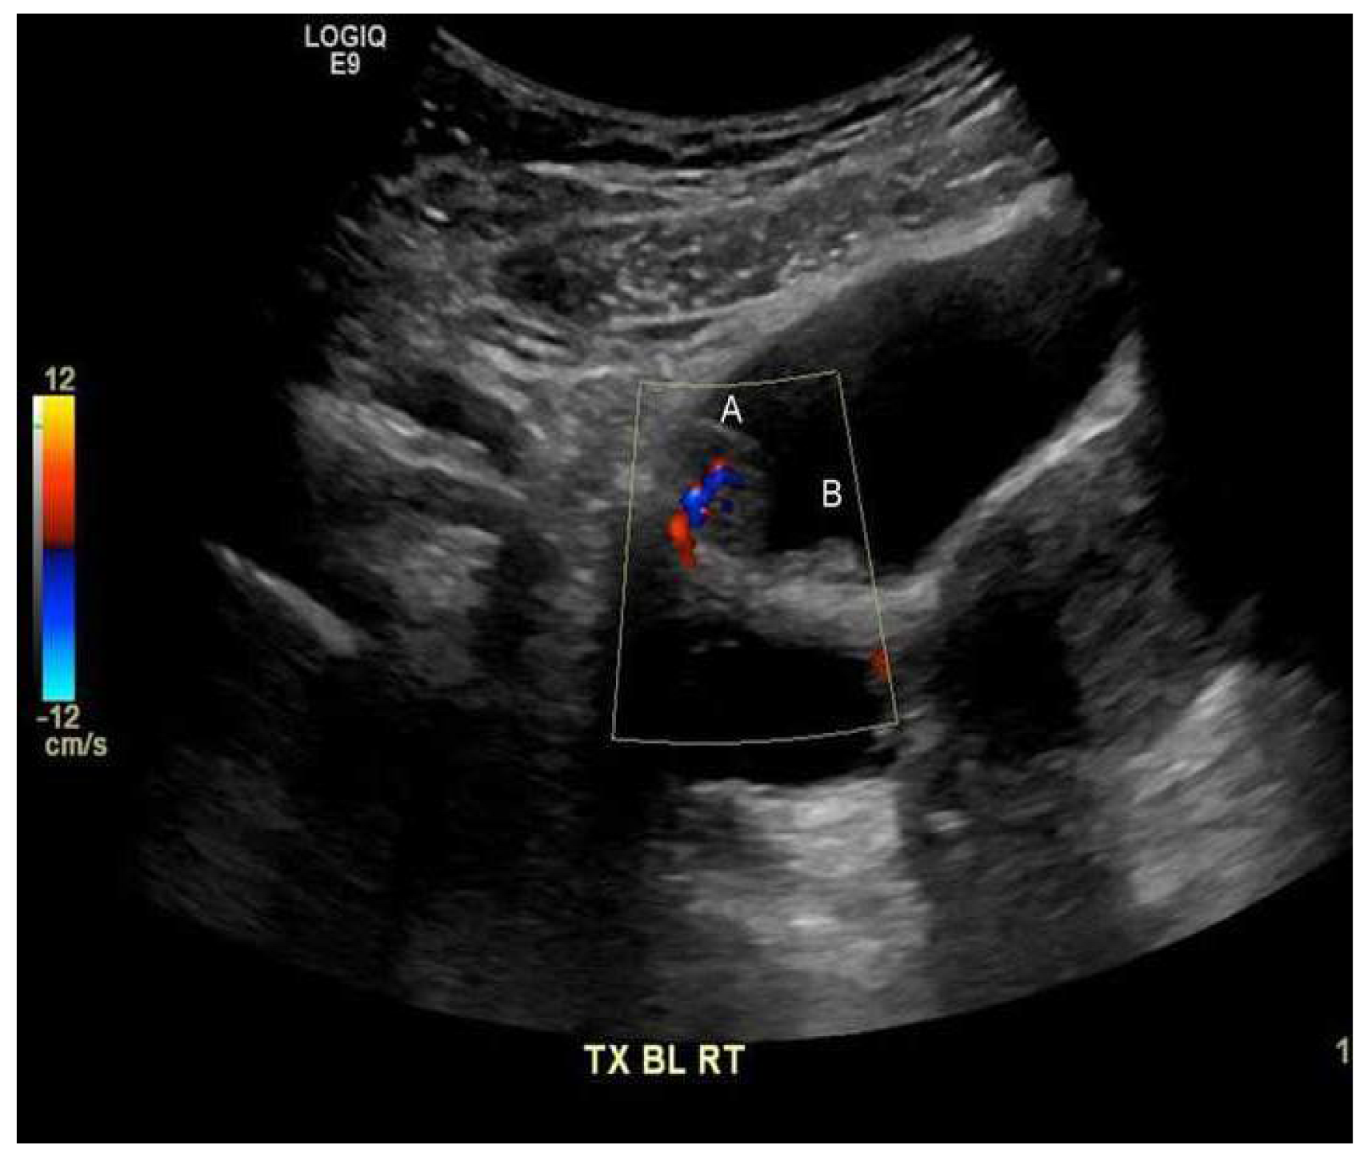

The urinalysis demonstrated a mild increase in the 21–50 red blood cells (20–50/HPF) and white blood cells (11–20 white blood cells/HPF). The urine cytology did not reveal any tumor cells, and the microscopic examination of the urine did not demonstrate any ova or parasites. Nitrites were not observed, and no growth was observed in the urine culture. The complete blood count revealed a white blood cell count of 5.7 × 109/L (range 4.5–11 × 109/L), hemoglobin 132 g/L (range 120–160 g/L), and platelets 381 × 109/L (range 140–440 × 109/L). The differential white blood cell count was normal, except for mild eosinophilia, with 1.15 × 109/L (range 0.0–0.4 × 109/L), or 18.0% (range 0.0–5.0%). The blood chemistry levels were all within normal ranges. A computerized axial tomographic scan (CT) of the abdomen and pelvis was performed and showed no pathologically enlarged lymph nodes. However, it revealed a 1.5 by 1.5 by 0.9 cm pedunculated intraluminal urinary bladder mass on the right side. The interpreting radiologist suggested that the mass could be better assessed by an ultrasound, which is shown in Figure 1. Although the ultrasound showed no stone, it raised concerns regarding possible bladder neoplasia. The patient underwent a cystoscopy with a transurethral resection of the mass for a histological assessment. The microscopic examination, as shown in Figure 2, revealed organisms that were morphologically compatible with the eggs of S. haematobium. We prescribed the patient 1200 mg of praziquantel orally every 12 h for one day (two doses). The one-month post-treatment follow-up included monitoring for eosinophilia and a microscopic examination of the urine (S. haematobium), which revealed a normal reading that confirmed that the patient had been cured.

Figure 1.

Polypoid lesion along the right anterior superior wall of the urinary bladder (A) 1.5 by 1.5 by 0.9 cm, with the internal flow on the color Doppler imaging suggesting that the mass has a blood flow. Medially, a smaller adjacent polypoid lesion (B) measuring 0.9 cm is noted.